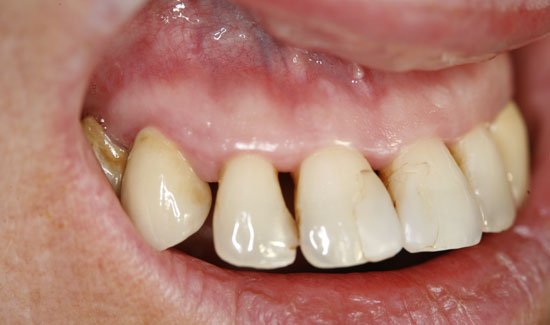

The patient introduced herself at our practice, inquiring about preserving the front teeth of her upper jaw, which were suffering from chronic periodontitis. We discovered general formation of pockets

(> 10 mm), spontaneous bleeding and a degree of tooth mobility of 2/3, i.e. the teeth were candidates to be extracted. As an interim solution (it was a public holiday) until restoration could take place, we offered local ozone gas treatment.

Fig. 3: Condition after ozone therapy. Chlorhexidine staining of the teeth